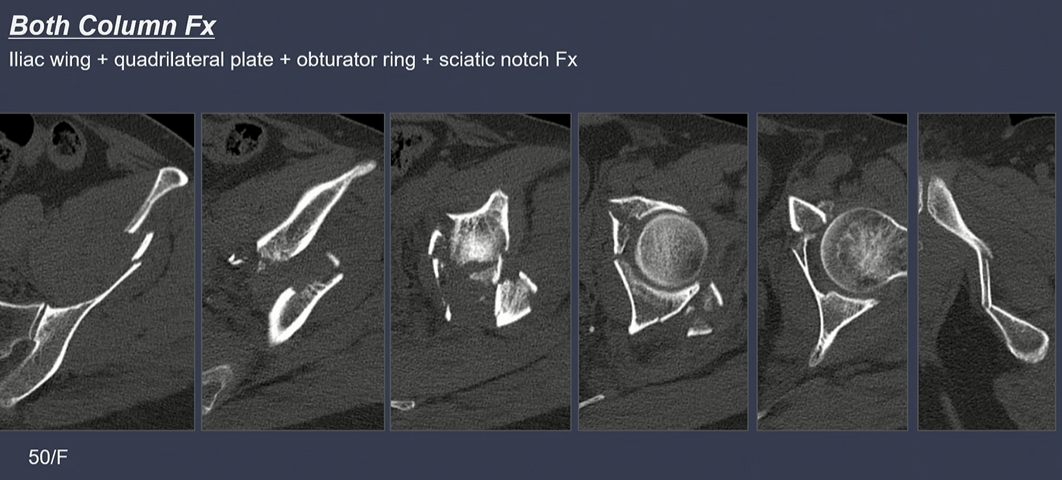

Spur sign은 both column fracture의 pathognomonic sign.